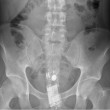

ROMA – Con il sesso i giochi erotici possono essere molto variegati. Questa “compilation” mostra però come a volte quei giochini finiscono male. Ecco infatti svariate radiografie eseguite negli ospedali di tutto il mondo.

Tutte queste persone sono state ricoverate con diversi oggetti incastrati nell’ano e non solo: dal cellulare alle chiavi di casa, passando per proiettili e giocattoli come macchinine e pupazzetti.